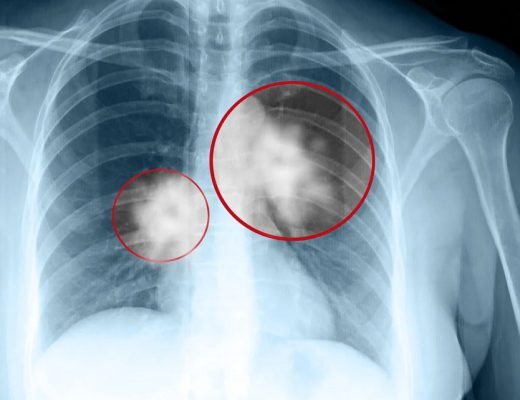

Cancerul pulmonar este una dintre cele mai întâlnite cauze ale deceselor cauzate de cancer, cu un procent de 18,2%. Deşi acest cancer este considerat în mod tradiţional ca fiind o ”boală a fumătorilor”, un procent surprinzător de 15-20% din cancerele pulmonare nou diagnosticate apar la persoane care nu au fumat niciodată, multe dintre acestea având între 40 şi 50 de ani.

Cu toate acestea, cea mai mare parte a cazurilor nu sunt depistate decât atunci când boala s-a răspândit în tot plămânul sau în alte părţi ale corpului (metastaze), moment în care tratamentele nu sunt la fel de eficiente.